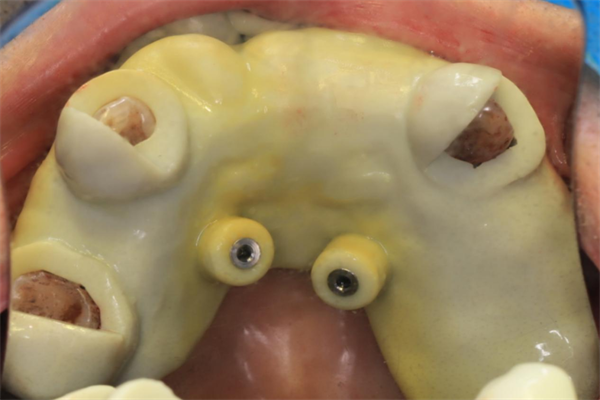

過渡義齒即刻戴牙(告別拔牙后缺牙期)